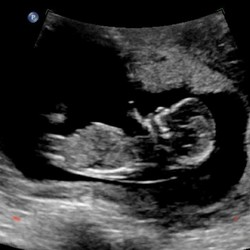

Wat verschrikkelijk zeg 😣 ik hoop echt voor jullie dat er toch een goede uitslag uit de test komt! Om misschien enigszins hoop te geven, iemand uit mijn omgeving kreeg ook bij de echo te horen dat het mis leek te zijn, de groei bleef achter, het hoofdje was veel te klein etc. Zij hebben de zwangerschap doorgezet en uiteindelijk was het kindje volledig gezond. 🍀🍀🍀